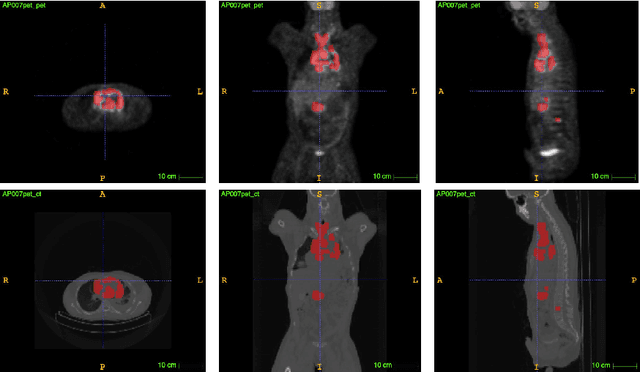

PET and CT are two modalities widely used in medical image analysis. Accurately detecting and segmenting lymphomas from these two imaging modalities are critical tasks for cancer staging and radiotherapy planning. However, this task is still challenging due to the complexity of PET/CT images, and the computation cost to process 3D data. In this paper, a segmentation method based on belief functions is proposed to segment lymphomas in 3D PET/CT images. The architecture is composed of a feature extraction module and an evidential segmentation (ES) module. The ES module outputs not only segmentation results (binary maps indicating the presence or absence of lymphoma in each voxel) but also uncertainty maps quantifying the classification uncertainty. The whole model is optimized by minimizing Dice and uncertainty loss functions to increase segmentation accuracy. The method was evaluated on a database of 173 patients with diffuse large b-cell lymphoma. Quantitative and qualitative results show that our method outperforms the state-of-the-art methods.